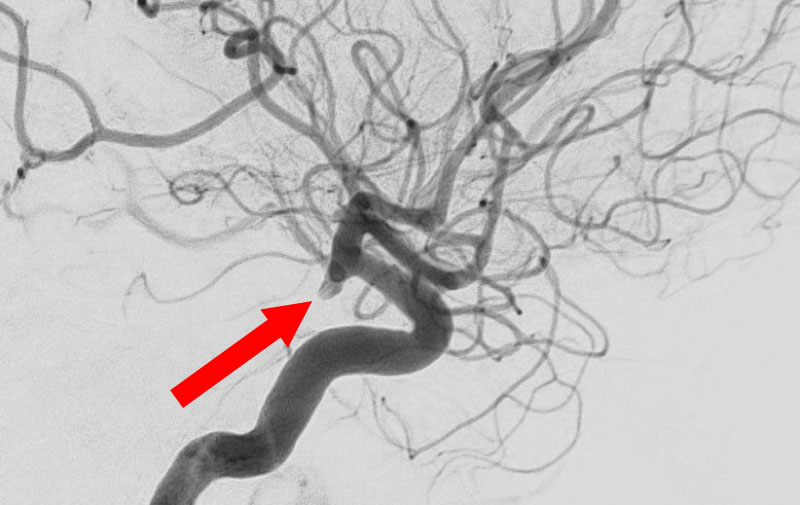

No.1593 手術後